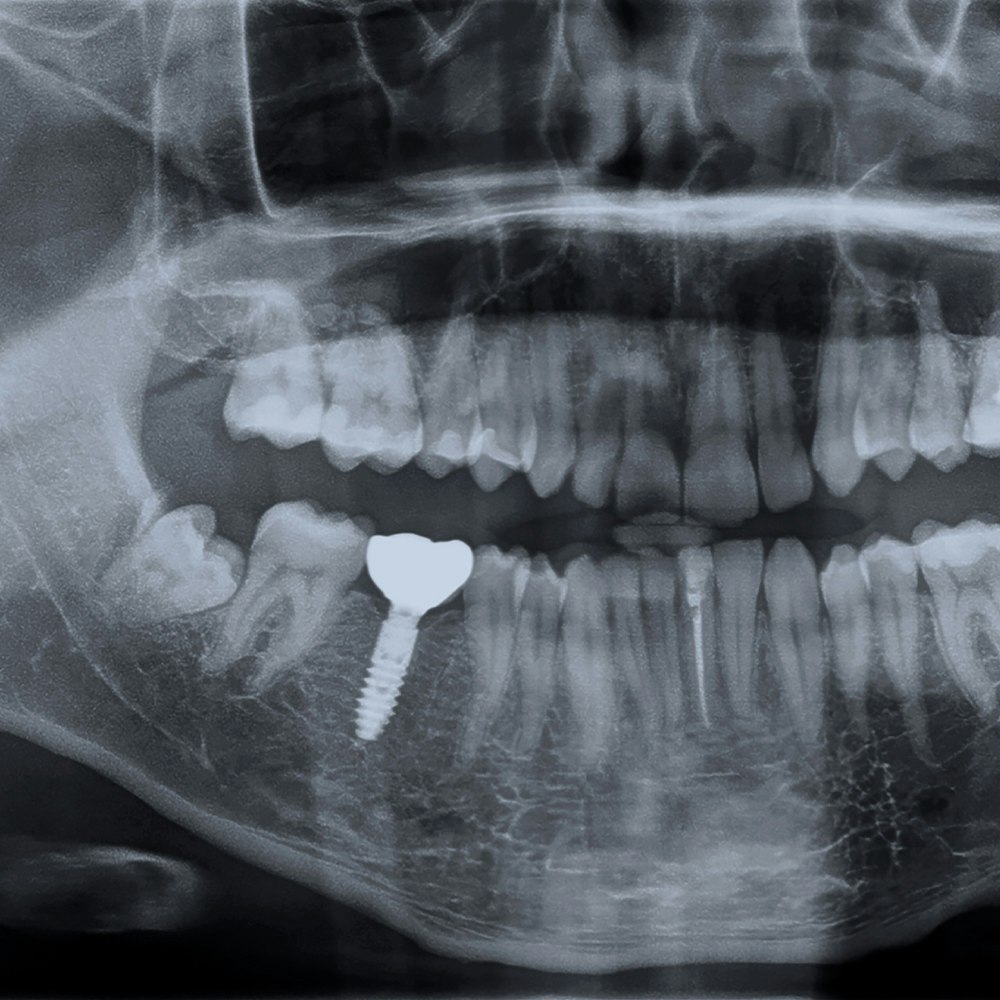

Your choice of dentist is the single most significant factor in cost. While some dentists may charge more than others, the fact is that investing in an experienced and reputable provider is the very best way to ensure the success of your implant procedure. Dr. Mohamed Saccoh is a member of the International Congress of Oral Implantologists who frequently places dental implants. He only uses the best dental materials and technology to ensure that your dental implant procedure provides maximum benefits.

Long-term tooth absence leads to bone loss in the jaw. In these cases, bone graft surgery must be performed to increase jawbone density before a dental implant can be placed. Fortunately, Dr. Saccoh can perform bone grafts at our office.